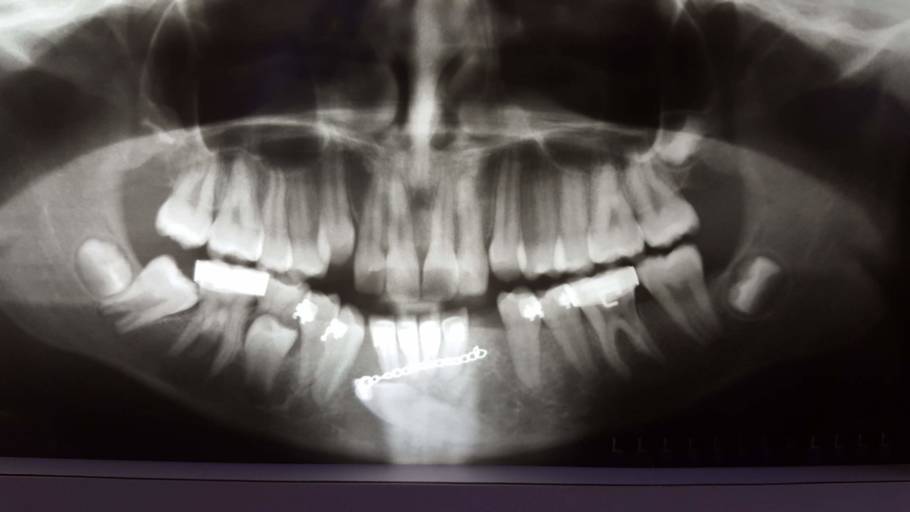

Another thing, it isn't when i bite down, but when i close my teeth kind of fast and hard, the molar on the bottom that sticks to the one on the top hurts. Here is how to know when to seek help. Intermittent pain when chewing could be the result of cracked or chipped teeth.

When a tooth is cracked, it becomes very painful to chew or bite food. As if i have multiple cavities. Braces hurt because they are changing the position of your teeth, whether pushing or pulling them or simply if you are trying to prevent strain on your teeth and jaw, stick with small bites of soft food like pudding. It feels like the sensation when you touch foil to your filling.